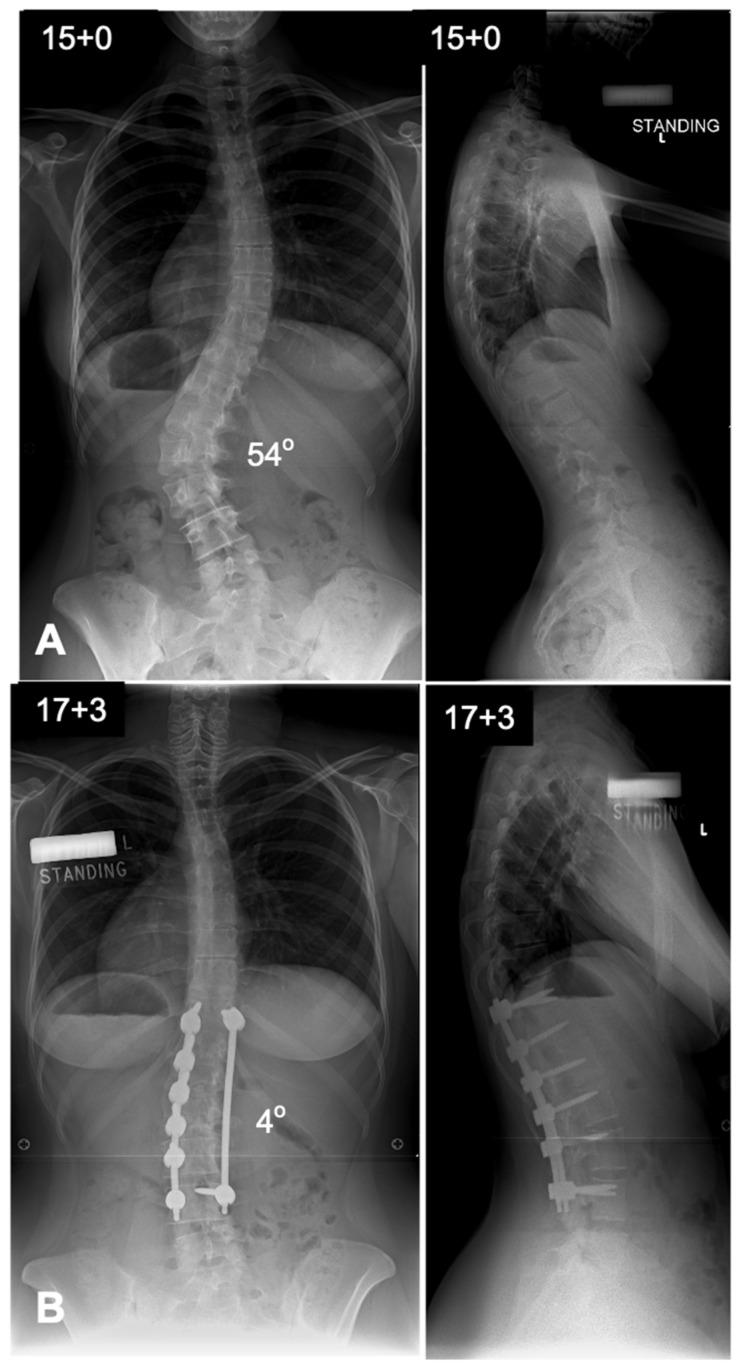

Surgical management of adolescent idiopathic scoliosis [AIS] is a complex undertaking with the primary goals to correct the deformity, maintain sagittal balance, preserve pulmonary function, maximize postoperative function, and improve or at least not harm the function of the lumbar spine. The evolution of surgical techniques for AIS has been remarkable, transitioning from rudimentary methods of spinal correction to highly refined, biomechanically sound procedures. Modern techniques incorporate advanced three-dimensional correction strategies, often leveraging pedicle screw constructs, which provide superior rotational control of the vertebral column. A number of surgical techniques have been described in the literature, each having its own pros and cons. This narrative review provides a detailed analysis of the contemporary surgical techniques used in the treatment of patients with AIS.

青少年特发性脊柱侧凸(AIS)的外科治疗是一项复杂的工作,主要目标是矫正畸形、维持矢状面平衡、保留肺功能、使术后功能最大化,以及改善或至少不损害腰椎功能。AIS外科技术的发展十分显著,已从基本的脊柱矫正方法转变为高度精细、生物力学合理的手术。现代技术采用先进的三维矫正策略,常利用椎弓根螺钉结构,从而对脊柱提供更好的旋转控制。文献中描述了多种外科技术,每种技术都有其优缺点。本叙述性综述对治疗AIS患者时使用的当代外科技术进行了详细分析。